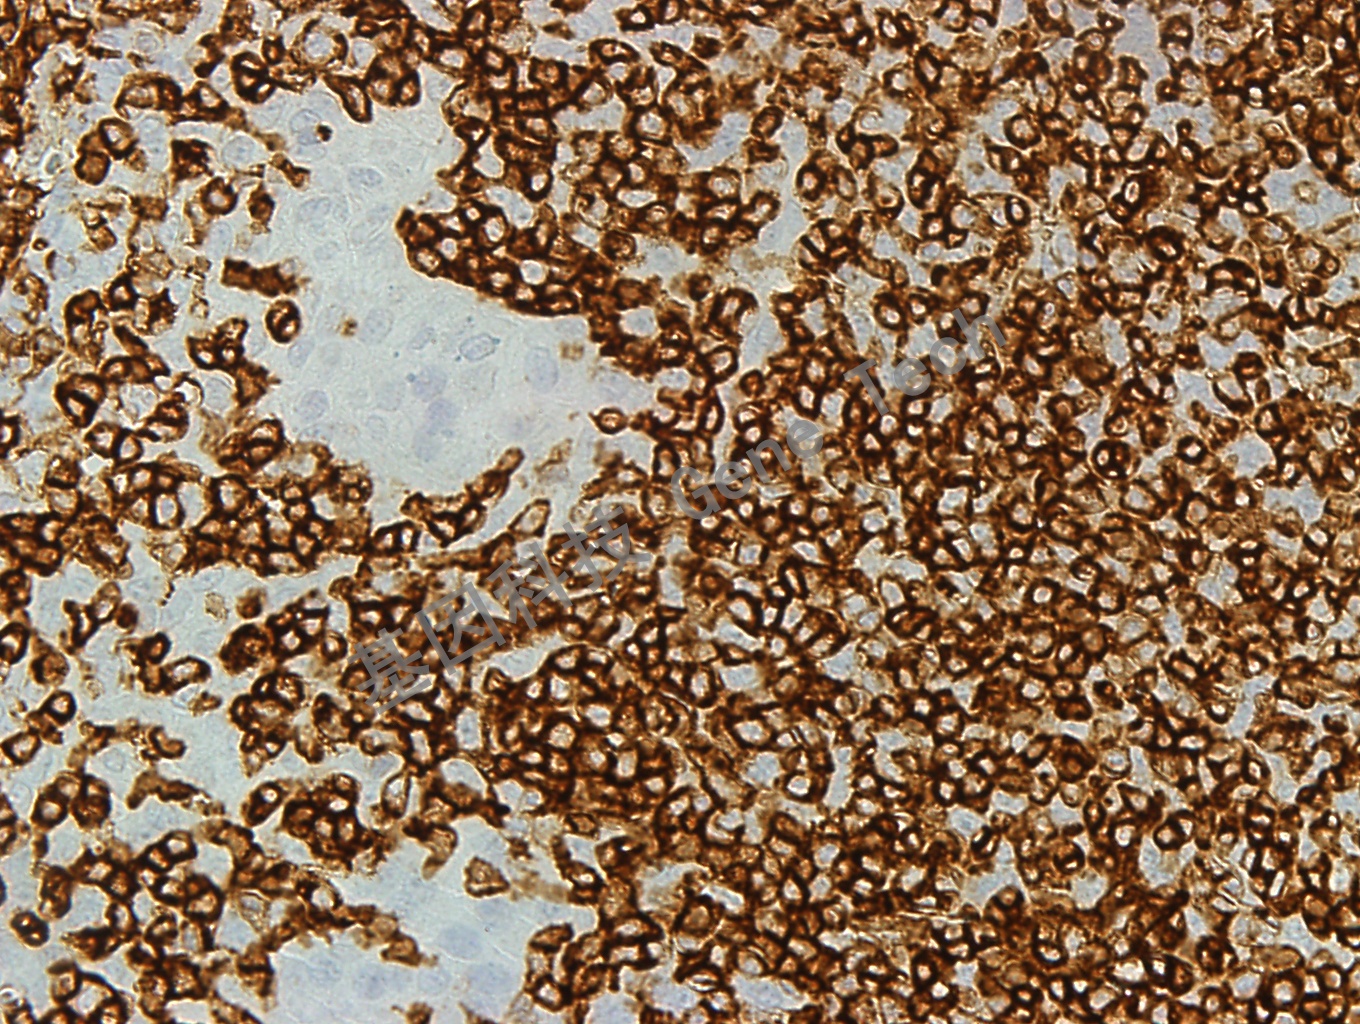

| 克隆號:PD7/26 | 陽性對照:扁桃體 | 陽性部位:細胞膜 |

| 預處理:高pH熱修復 | 適用:石蠟切片/冰凍切片 | 顯色系統:GTvisionTM |

| 簡介:人淋巴細胞表面的CD45 分子因其剪切形式不同有5 中蛋白形式依次為:CD45RO、RB、RA、RBC 和RABC,其分子量(不計糖鏈)分別是180、190、195、205 和220kDa。其中CD45RB 表達在B 細胞、某些T 細胞亞群、單核細胞、巨噬細胞中,粒細胞中表達較弱。CD45 抗體PD7/26 克隆是出現于上世紀80 年代初經典克隆, 能夠與5 種CD45 蛋白的3 種類型 (分子量為 190,205 和220 kDa)結合。其提示意義基本同CD45,但在Langerhan’s 細胞與小部分T 細胞中不表達。 | ||

| 扁桃體石蠟切片,用 CD45RB(GT2219)染色,細胞膜陽性,DAB 顯色。(40X) | ||